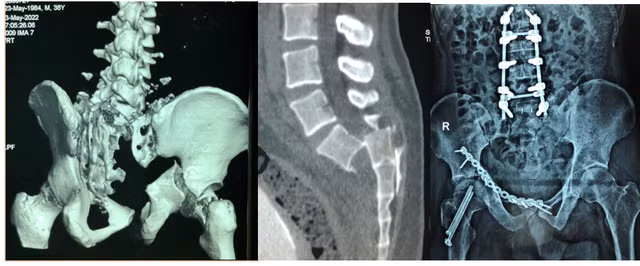

![]() |

| Hình ảnh gãy trật rất nặng khung chậu, cột sống và mổ cột sống với hơn 2 tháng nằm viện của bệnh nhân Khoa. Ảnh: BSCC |